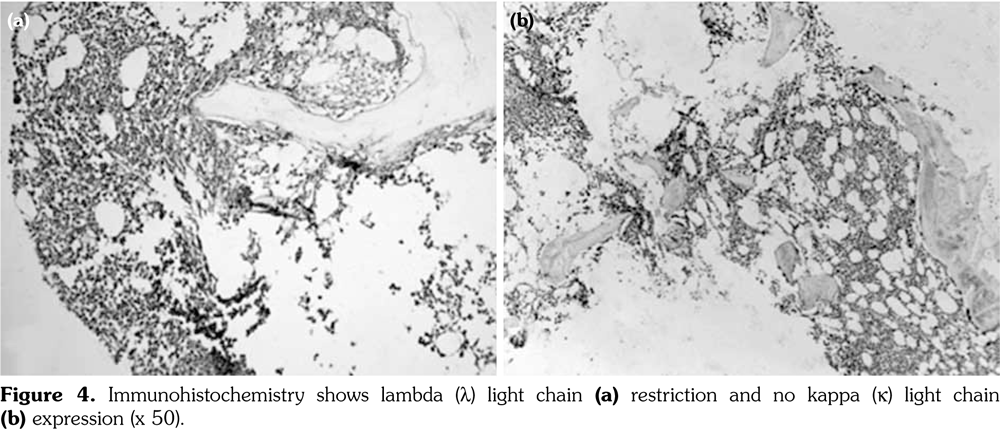

Two years later, the patient presented with an ulcer on the left nasolabial groove. Skin biopsy of the affected tissue revealed damaged epidermis with basal-cell carcinoma infiltration in the dermis (Figure 1), suggesting basal-cell carcinoma for which she underwent a resection. There were no clinical or laboratory signs suggestive of DM activity.